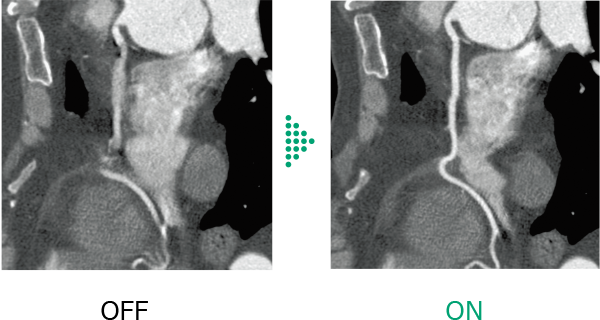

In head scanning, Body motion Correction corrects artifacts caused by patient movement.